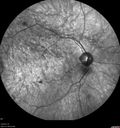

Congenital Hypetrophy of the Retinal Pigment Epithelium (CHRPE)621 views63 year old female with normal vision and CHRPE lesion in the right eye.Apr 27, 2020

Congenital Hypetrophy of the Retinal Pigment Epithelium (CHRPE)381 views63 year old female with normal vision and CHRPE lesion in the right eye.Apr 27, 2020

Congenital Hypetrophy of the Retinal Pigment Epithelium (CHRPE)365 views63 year old female with normal vision and CHRPE lesion in the right eye.Apr 27, 2020

Congenital Hypetrophy of the Retinal Pigment Epithelium (CHRPE)375 views63 year old female with normal vision and CHRPE lesion in the right eye.Apr 27, 2020

Congenital Hypetrophy of the Retinal Pigment Epithelium (CHRPE)376 views63 year old female with normal vision and CHRPE lesion in the right eye.Apr 27, 2020

Congenital Hypetrophy of the Retinal Pigment Epithelium (CHRPE)432 views63 year old female with normal vision and CHRPE lesion in the right eye.Apr 27, 2020